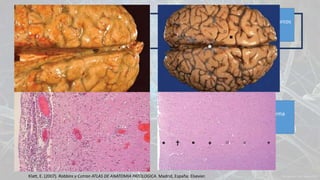

Anatomía patológica

Opacidades pardo-amarillentos que borran los surcos

y corresponden al exudado inflamatorio

Infiltrado de neutrófilos, vasos dilatados, edema

cerebral

Klatt, E. (2007). Robbins y Cotran ATLAS DE ANATOMIA PATOLOGICA. Madrid, España: Elsevier.